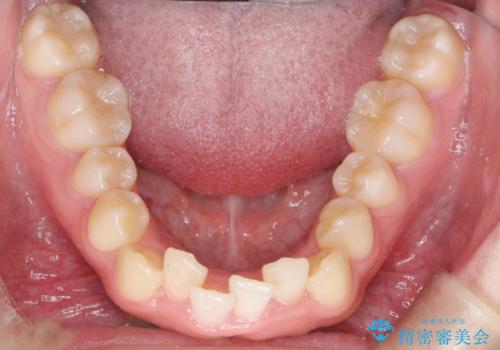

インビザラインでの前歯のガタガタの矯正

- 上下の前歯のがたつきを主訴に来院されました。

歯と歯の間をわずかに削りスペースを作り、インビザラインにて矯正治療を行うこととしました。